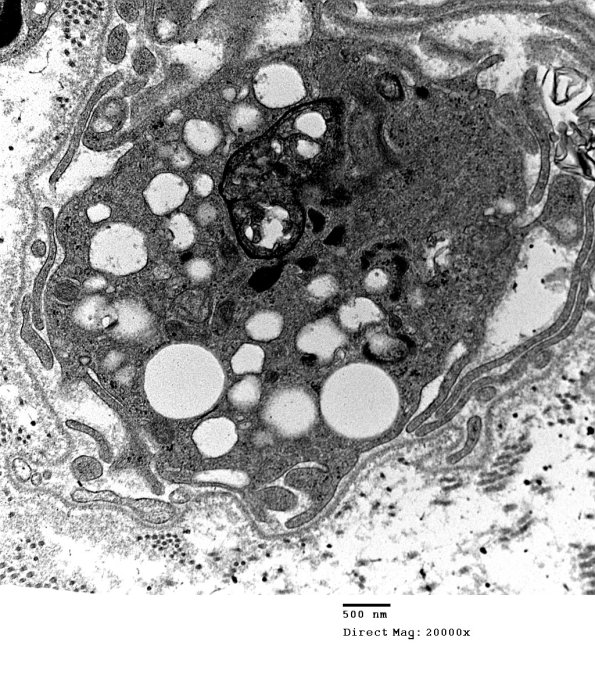

3F2 Axonal Degeneration (Case 10) 006 - Copy

Higher magnification of image #3F1. (electron micrograph)